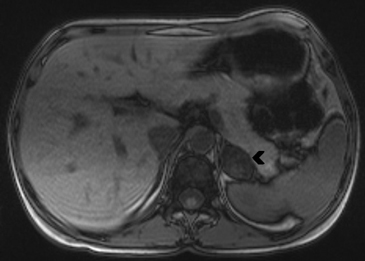

En la TC no contrastada las glándulas suprarrenales normales son homogéneas y simétricas, con una densidad muy similar a la del parénquima renal adyacente (Figura 1 a). Con un medio de contraste ev la glándula suprarrenal se opacifica en forma homogénea, similar al hígado o al bazo (Figura 1 b). Si la cantidad de tejido adiposo retroperitoneal es abundante las glándulas suprarrenales pueden aparecer enteramente rodeadas por grasa y su delimitación es más fácil (Figura 2 a); lo inverso ocurre en pacientes muy delgados con escasa grasa retroperitoneal (Figura 2 b). En RM, en secuencias ponderadas en T1 y T2 convencionales tienen una intensidad de señal homogénea, hipointensa respecto de la grasa adyacente e iso o hipointensa con respecto del parénquima hepático (Figura 3 a y b). En los cortes coronales se aprecia mejor la forma y la posición de las glándulas suprarrenales (Figura 3 c).

Figura 3. Glándula suprarrenal normal en resonancia magnética. (a) Cortes axial ponderado en T1 la señal de la glándula normal (flecha negra) es hipointensa respecto a la grasa retroperitoneal e isointensa respecto al parénquima hepático. (b) Cortes axial ponderado en T2 en que se muestra la glándula suprarrenal derecha (flecha blanca) y (c) corte coronal ponderado en T2 en que se muestra la glándula suprarrenal derecha (flecha blanca) y la glándula suprarrenal izquierda (flecha negra) con similares características de intendidad de señal. 3. Causas y prevalencia de las lesiones suprarrenales